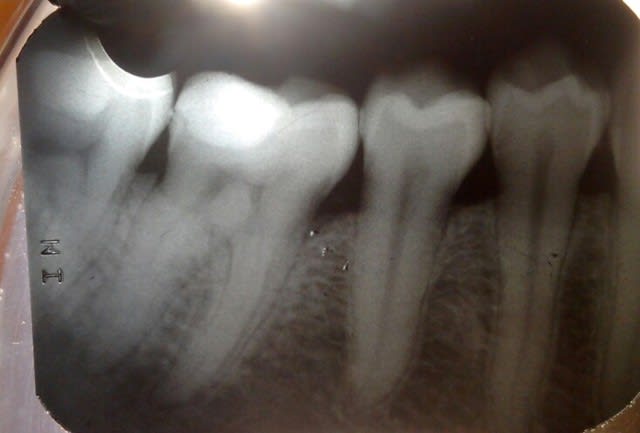

Ma patiente est âgée de 26ans, aucun problème de santé générale.

Elle n'avait aucune douleur initialement et après un bite wing en secteur 4 j'ai mis en évidence une carie distale sur 46.

J'ai réalisé une restauration composite sous digue, 2 mois après la dent était toujours très sensible au froid et douloureuse à la mastication. La patient a une très bonne hygiène, pas d'inflammation gingivale et les points de contacts entre 45 46 et 47 sont ok.

Nous sommes un mois et demi après cette restauration et rien n'a changé. Douleurs à la mastication et au froid, la patient ne mange plus de ce côté et ne prends plus d'eau froide. La percussion est normale, le sondage parodontal est normal, pas de sur-occlusion.

et pourquoi pas nécrose de la 6, j'ai l'impression qu'il y a un élargissement ligamentaire aux apex.

LA 6 n'est pas nécroisée, le test de sensibilité au froid est douloureux. Et malgé peut-être l'impression d'un léger élargissement desmondontal sur la 6, la percussion est identique sur la 6 et la 7, RAS.